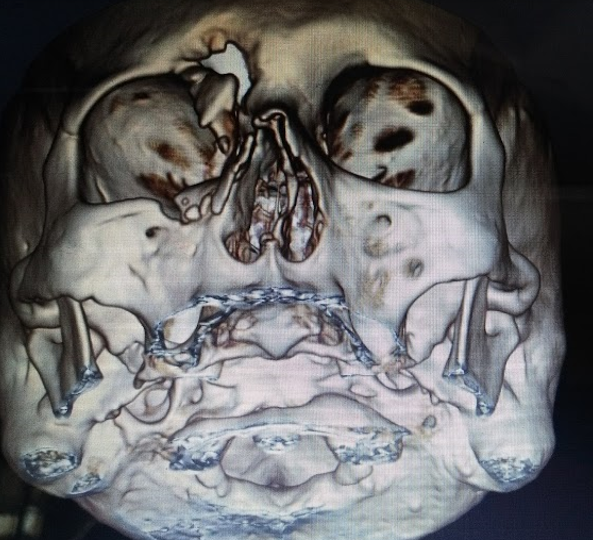

Paciente masculino de 49 años de edad procedente de área urbana refiere inicio de enfermedad actual de 1 día de evolución cuando presentó dolor y disminución de la agudeza visual posterior a trauma directo con objeto expedido a alta velocidad, por lo que consulta.